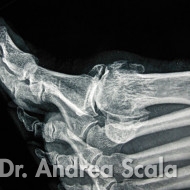

IMG 2 – La radiografia mostra un alluce rigido più grave l’alluce ed il 1° metatarso sono quasi in contatto.